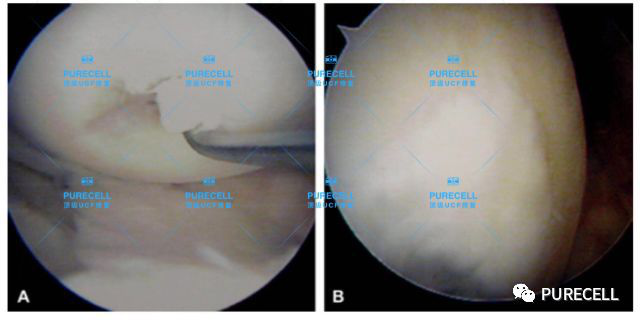

PURECELL首席科學家以及運動醫療專家已經驗證了UCF對膝關節修復的有效性,下圖是UCF軟骨及半月板修復前後影像對比。

圖片12.png

圖片13.png